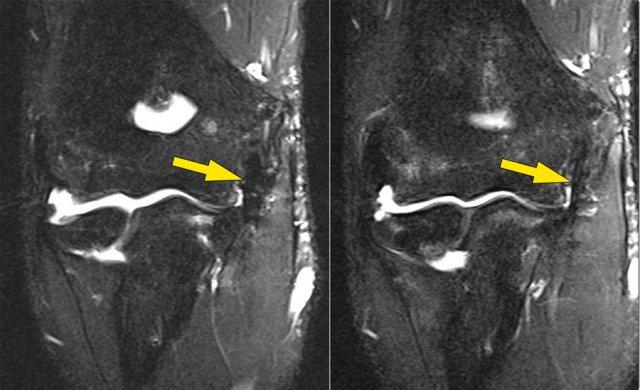

Ở đây chúng ta thấy hai hình ảnh mặt phẳng coronal liên tiếp của dây chằng bên trụ (UCL).

Bình thường có thể thấy một số tín hiệu cao ở phần gần (mũi tên).

Hãy chú ý cách nó bám chắc vào củ sublime và so sánh với các hình ảnh tiếp theo.

UCL tear

Hãy nhớ rằng dây chằng UCL phải bám rất chắc vào củ sublime.

Trong trường hợp này thì không như vậy, vì vậy ngay cả trên hai hình ảnh này bạn có thể nhận thấy rằng có một rách hoàn toàn.

Lưu ý rằng có một số phù tủy xương ở củ sublime.